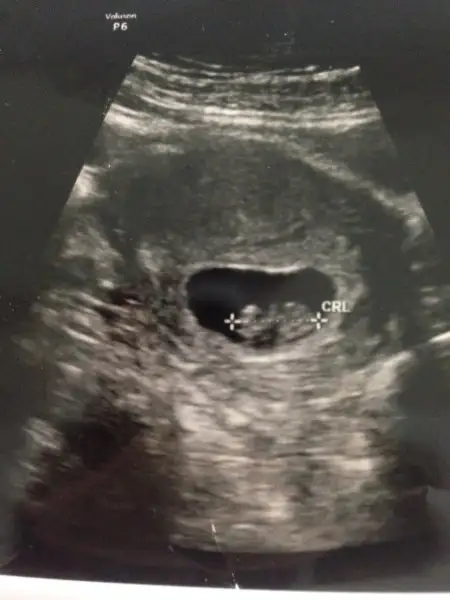

Bu 8. Haftada karindan cekildi canim.yorumlarsan sevinirim

BİZİ de yorumlayabilir misiniz 8 haftalik usgmiz :KK66:) teşekkürler simdiden. Karindan usg.